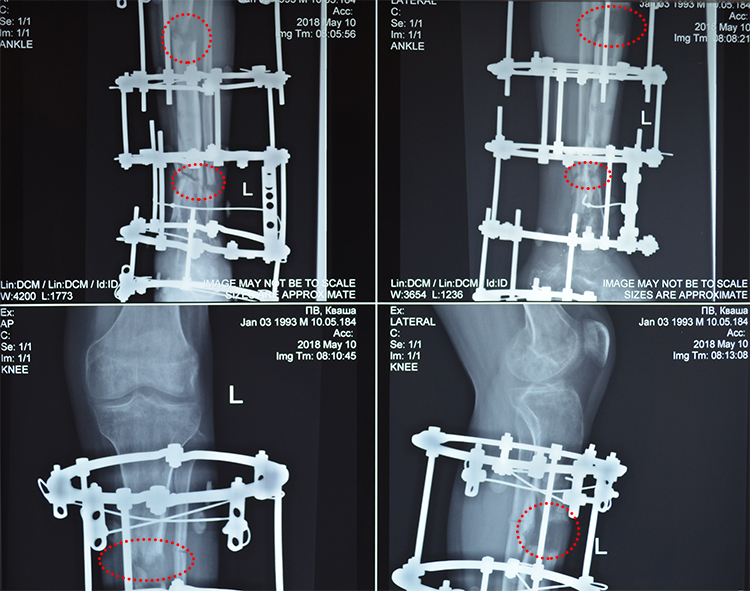

The performed surgery proved to be rather complicated as the surgeons were working on Petro’s leg for about 4 hours. Still the newly taken x-ray testified that it has been a worthy effort – there can be seen formation of the bone’s regenerated tissue in the places of stretching and deformation removal. Of course, it is still too early to uninstall the apparatus, but the positive momentum fills us with confidence that Petro will get well soon. The next examination is due in about two months’ time.

In the place of stretching and deformation removal, regenerated tissue can be seen